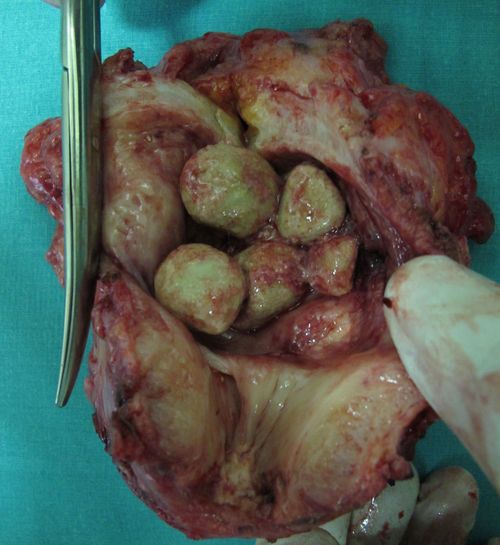

Фитобезоар ("камень из пищевого комка") в кишке